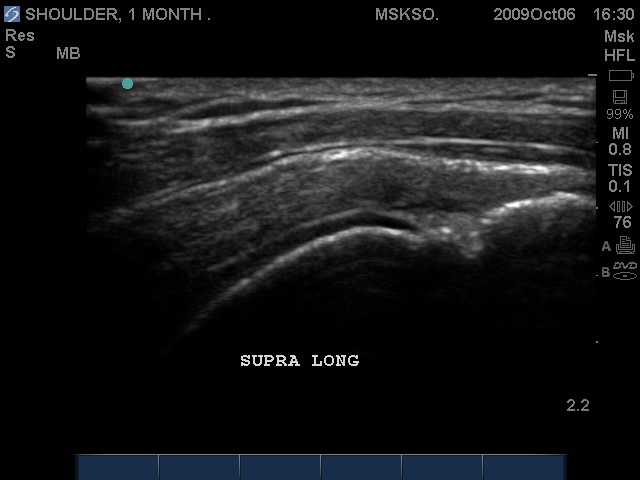

Long axis Bicep tendon with synovial fluid at level of surgical neck

Long axis Supraspinatus tendon over lateral Greater Tuberosity. (lateral greater tuberosity is flat relative to the anterior) Tendon retraction is seen over cartilage interface sign of the humeral head.

Slightly anterior movement of the probe to visualize the full detail of the tear only for this case study purpose.